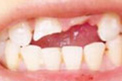

• 牙齿缺损

• 间隙牙

• 畸形牙

• 牙釉质发育不全